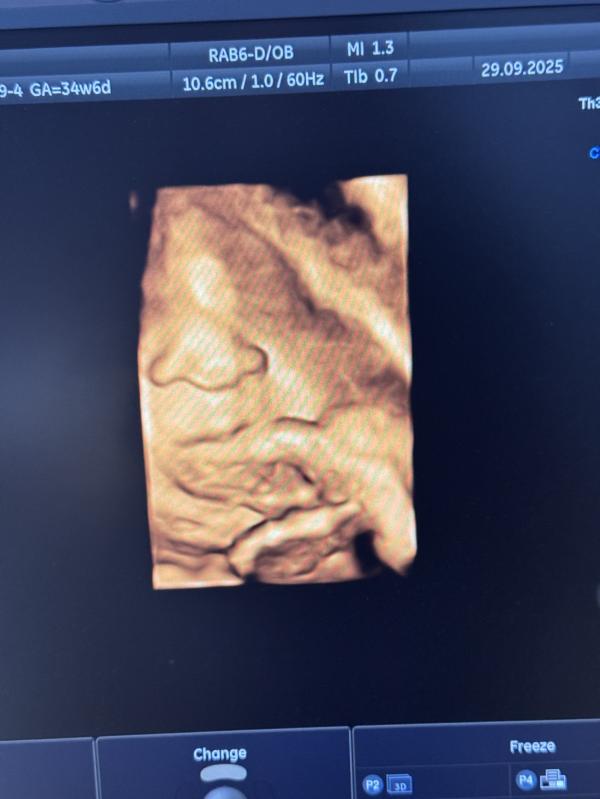

А это наша щекастая бусинка ,которая уже весит 3100+-300 гр🤣

Сказали ,что 15 числа на прием + узи и если что будут родоразрешать 20-21 октября (это будет 38 недель),тк плод крупный ,чтобы мне не тяжело было рожать 🥹